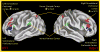

The challenge in understanding cognitive impairment in schizophrenia is that people with this illness have deficits in an array of domains. Here, we briefly review evidence regarding the pattern of deficits within three domains: context processing, working memory and episodic memory. We suggest that there may be a common mechanism driving deficits in these domains - an impairment in the ability to actively represent goal information in working memory to guide behavior, a function we refer to as proactive control. We suggest that such deficits in proactive control reflect impairments in dorsolateral prefrontal cortex, its interactions with other brain regions, such as parietal cortex, thalamus and striatum, and the influence of neurotransmitter systems, such as dopamine, GABA and glutamate.